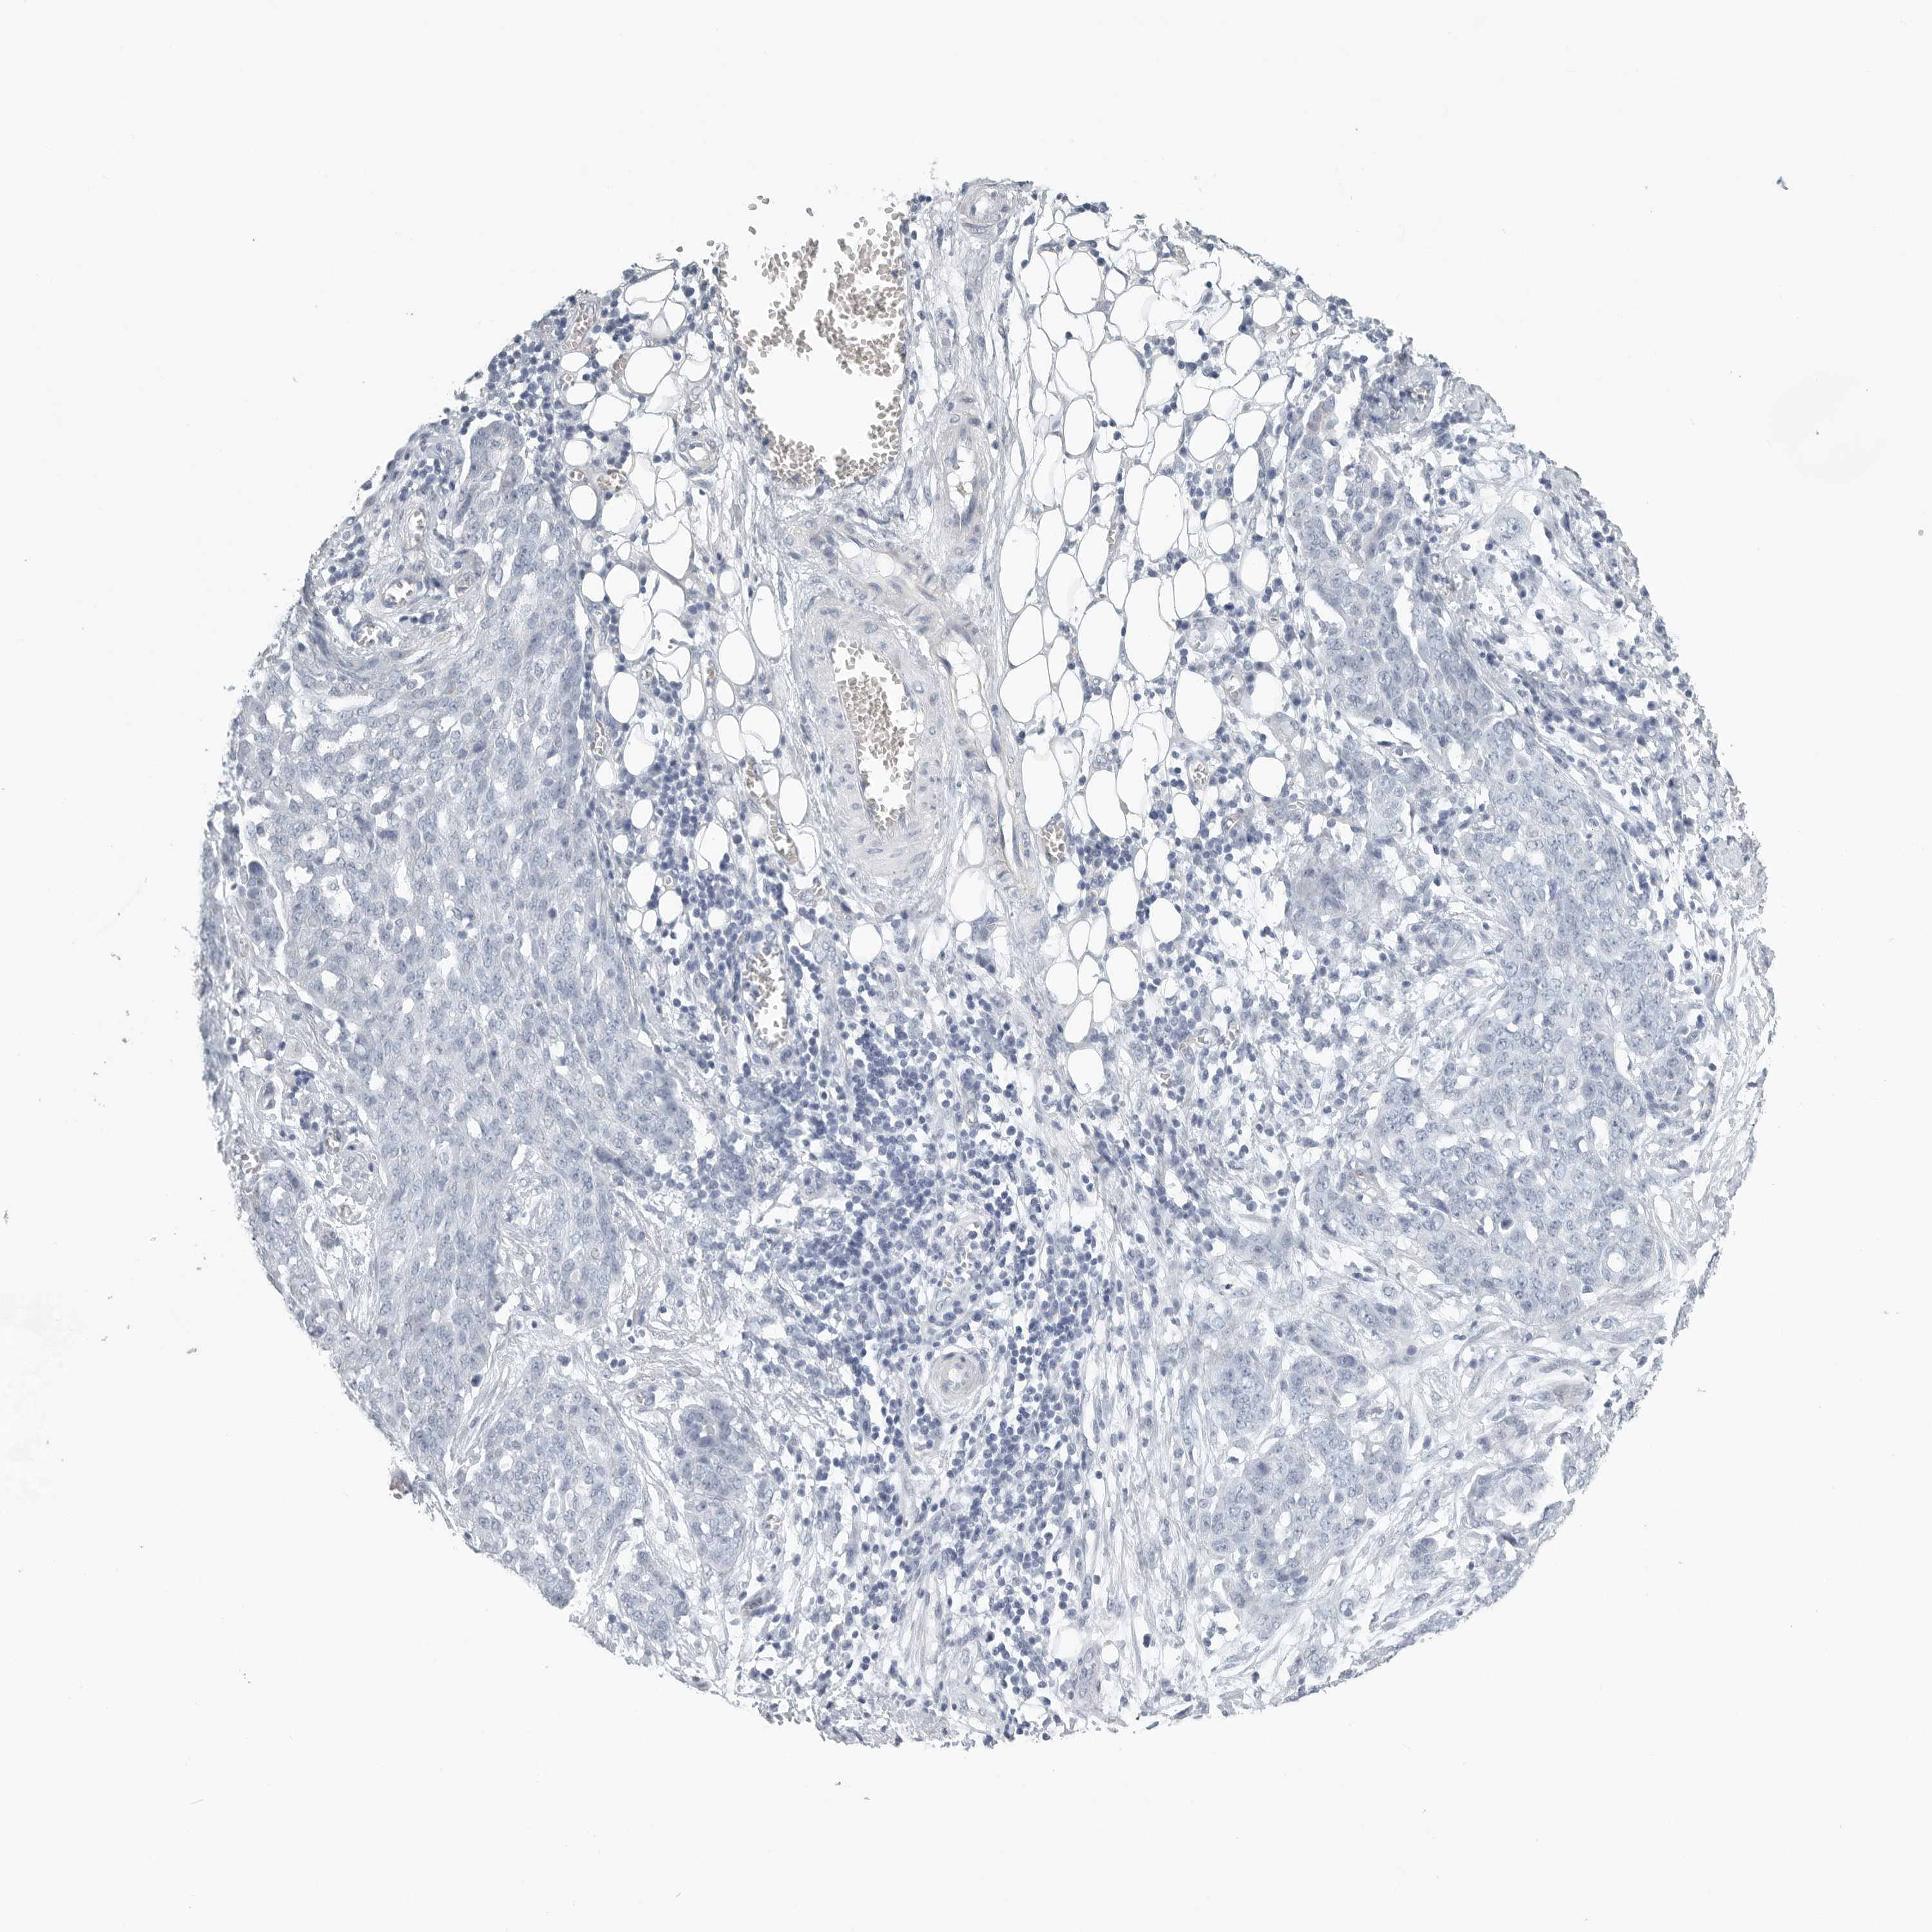

OVARIAN CANCER - Protein expressioni

A mouse-over function shows sample information and annotation data. Click on an image to view it in a full screen mode. Samples can be filtered based on level of antibody staining by selecting one or several of the following categories: high, medium, low and not detected. The assay and annotation is described here.

Note that samples used for immunohistochemistry by the Human Protein Atlas do not correspond to samples in the TCGA dataset.

Antibody stainingi

Antibody staining in the annotated cell types in the current human tissue is reported as not detected, low, medium, or high, based on conventional immunohistochemistry profiling in selected tissues. This score is based on the combination of the staining intensity and fraction of stained cells.

Each image is clickable and will lead to virtual microscopy that enables deeper exploration of all samples and also displays staining intensity scores, fraction scores and subcellular localization as well as patient and tissue information for each sample.

Antibody HPA027134

Antibody HPA027150

Antibody HPA029859

Antibody CAB022343

Cystadenocarcinoma, serous, NOS

Carcinoma, endometroid

Cystadenocarcinoma, mucinous, NOS

Carcinoma, NOS